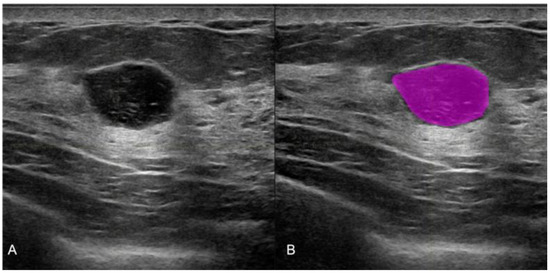

All of the pre-biopsy images of the lesions were acquired with a Samsung RSV80A or RSV85 Healthcare, Seoul, Republic of Korea. All 365 selected images were used for radiomic analysis. Manual segmentations were performed with the LifeX program [16] by three different radiologists, as shown in Figure 1.

Figure 1. Manual ultrasound image segmentation on LifeX software. (A) Round shape breast lesion in the US conventional B mode, (B) the manual segmentation with colored ROI obtained with LifeX software. The histological result of the biopsy was that of a fibroadenoma.